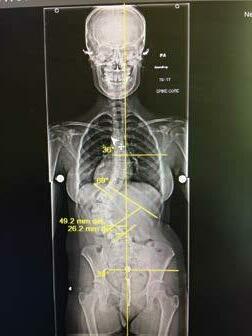

Dr. Yevgeniy Khavkin, the founder of Khavkin Clinic, was raised in Moscow, Russia. He was Inspired to go into the medical field by his mother, a pediatric surgeon, and started his exposure to medicine at age 14 by assisting his mother in surgeries.

Dr. Khavkin started medical school in Moscow when he was 16 and, after his family relocated to the US, transferred to medical school at the University of Chicago, where he also completed his neurosurgical training.

After finishing spine fellowship at Johns Hopkins University, Dr. Khavkin became the director of the neurosurgical spine program at Northwestern University before moving to Las Vegas in 2010. One of only a few fellowship trained spine neurosurgeons in Las Vegas, Dr. Khavkin pioneered a number of spine surgery techniques and was the first surgeon in Nevada to perform complex spine oncological procedures such as sacrectomies and en bloc spondylectomies.

Dr. Khavkin: Khavkin Clinic is a multispecialty practice that includes Las Vegas Neck and Back, Las Vegas Sinus and Las Vegas Headache. We pride ourselves on the comprehensive approach to the diagnosis and treatment of the diseases of the nervous system and the spine.

Even though my expertise is in spine surgery, most of our patients fortunately do not require any surgical treatment and we guide them down the non-surgical path to make sure they get better and return to the pain free life.